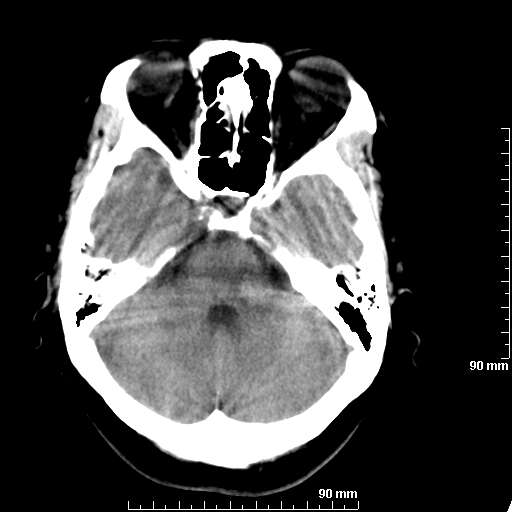

我院西门子单排CT由于一零件受损而产生的伪影.

哈哈,都不是。是虑线器fiter裂损。大家没想到吧。

哦,跟脑出血有点像哦

形状不规则,边缘模糊。比较特殊的一种伪影哈!

这种伪影很常见!伪影应该是在视野的中心的。

西门子的虑线器fiter裂损这才是很难见的问题,GE的最常见

虑线器老化,中间崩裂一块掉了